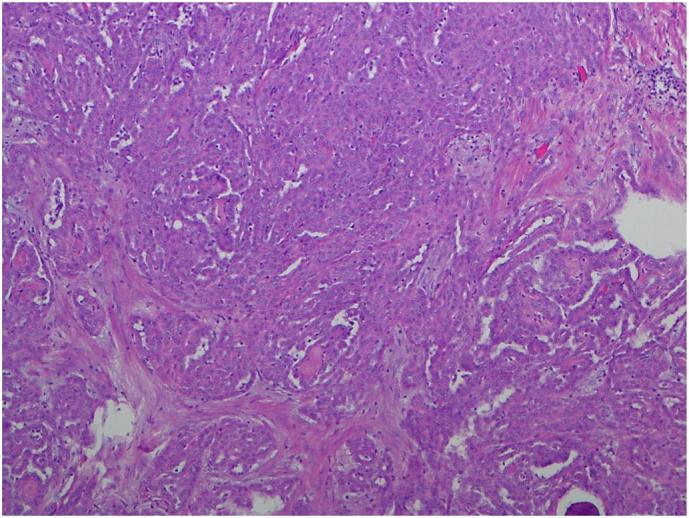

•Incidental finding of a fallopian tube lesion at the time of bilateral salpingectomy•Histopathological appearance not consistent with mucinous or serous carcinoma, appearance of mesothelioma•Very rare known primary neoplasm of tubal mesothelium, favours an indolent course•Recommendation for prophylactic hysterectomy and bilateral oophorectomy•If nil further spread, generally nil further treatment is required.

•双侧输卵管切除术时偶然发现输卵管病变

•组织病理学表现不符合黏液性或浆液性癌,符合间皮瘤表现